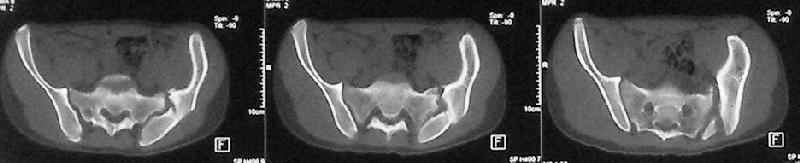

Учитывя наличие участков сращений, помогите опредилиться с тактикой.

Наш план пока такой: 1. выполнить остеотомии в участках сращений 2.постепенно аппаратом низвести смещенную половину таза. 3.выполнить внутренний остеосинтез передних и задних отделов.

Будем признательны за ваш взгляд на тактику леченияэтого больного, а так же на такие проблемы как: места остеотомий, возможные варианты компоновки аппарата, выбор имплантатов для последующего вмешательства.